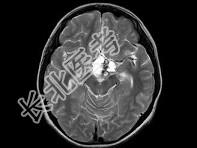

- 单项选择题女,18岁, 发育不良伴口渴,多饮、多尿10余年, 根据所提供图像,最可能的诊断是 ( )

C、颅咽管瘤